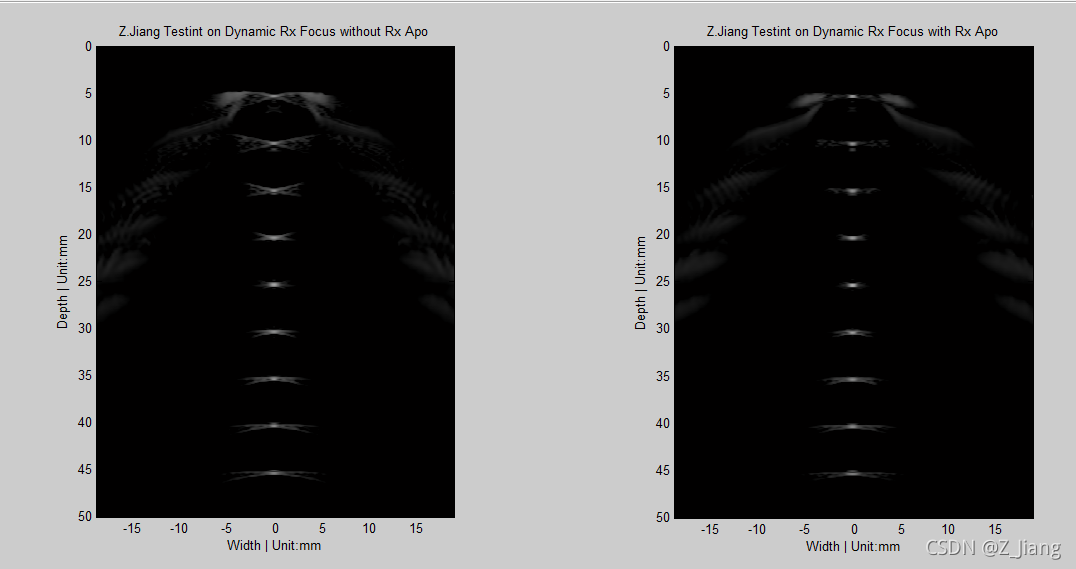

所谓Apodization是指探头在发射/接收信号时,给与不同阵元不同的权重,从而使得波束合成的效果更好。根本原因是,阵元具有指向性,垂直阵元方向上信号不管发射还是接收端SNR最高,于是我们赋予更高的权重。我们可以在发射做Apo,也可以在接收做Apo,或者两者都做,我在Rx时对比一下有无Apo的区别,见下图

接收动态聚集无Apo(左)接收动态聚集有Apo(右)

怕看不清楚,放大些,怼近看

放大看 接收动态聚集无Apo(左)接收动态聚集有Apo(右)